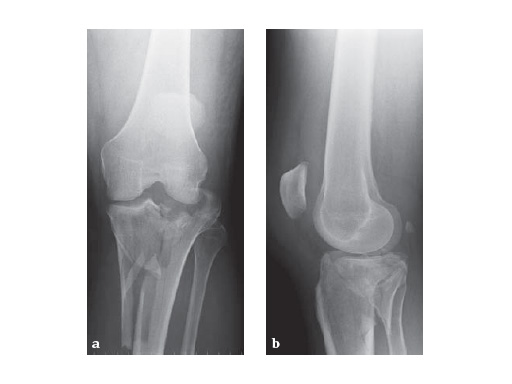

The LCP Medial Proximal Tibia Plates 3.5 and 4.5 are part of the LCP periarticular plating system. They are intended to buttress metaphyseal fractures of the medial tibia plateau, split-type fractures of the medial tibia plateau, medial split fractures with associated depressions and split or depression fractures of the medial tibia plateau. The plates may also be used for fixation of the proximal quarter (lateral and medial) of the tibia as well as segmental fractures of the proximal tibia. The 4.5 version may also be used for fixation of nonunions and malunions of the medial proximal tibia and tibia shaft, as well as opening and closing wedge tibial osteotomies.

57-year-old malemotor accident

Case provided by Phil Kregor, Nashville, USA